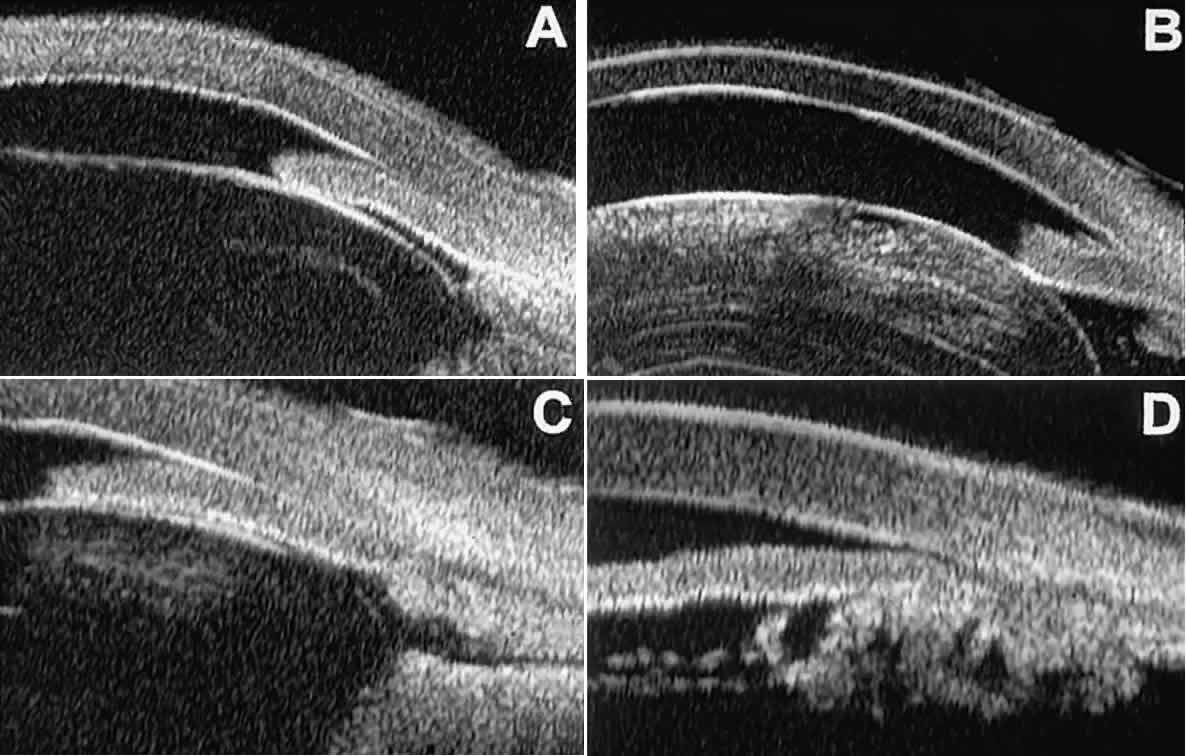

The role of UBM in the preoperative assessment of eyes with cataract is as yet unknown. In certain eyes, however, UBM may reveal features or abnormalities that could alter the ophthalmologist's surgical approach. Postoperatively, UBM can show the size and location of an intraocular lens (IOL) and the positioning of the haptics. A posterior chamber IOL appears on UBM as a highly reflective plate (corresponding to the lens optic) in the retropupillary plane with reverberation artifacts behind it (Fig. 17A). In contrast, an anterior chamber IOL appears on UBM as a sonoreflective plate located anterior to the pupillary plane (see Fig. 17B). In most eyes with a posterior chamber IOL, UBM can show whether the haptics are in the capsular bag (Fig. 18A), in the ciliary sulcus (see Fig. 18B), or in some other anatomic location12 (e.g., resting on the peripheral iris or secured with sutures to the sclera). The haptics are easier to locate if they are made of polymethyl-methacrylate than if they are made of proline because the former has a stronger reflectance.

Fig. 17. Composite UBM images of intraocular lenses. A. Posterior chamber IOL. B. Anterior chamber IOL.

Fig. 18 . Localization of posterior chamber IOL haptics by UBM. A. Haptic in capsular bag (arrow). B. Haptic (bright object just behind peripheral iris) in iridociliary sulcus.

Ultrasound biomicroscopy appears to be helpful postoperatively in determining the extent of postoperative complications of cataract surgery such as serous choroidal detachment (see Fig. 13A), iridocapsular adhesion (Fig. 19A), postoperative hyphema (see Fig. 19B), stripping of Descemet's membrane (see Fig. 19C), and wound gaping (see Fig. 19D).

Fig. 19. Complications of cataract surgery revealed by UBM. A. Capsular adhesion to midzone of iris. B. Postoperative hyphema. Clot appears denser than aqueous with suspended blood cells. C. Stripping of Descemet's membrane. D. Wound gape.